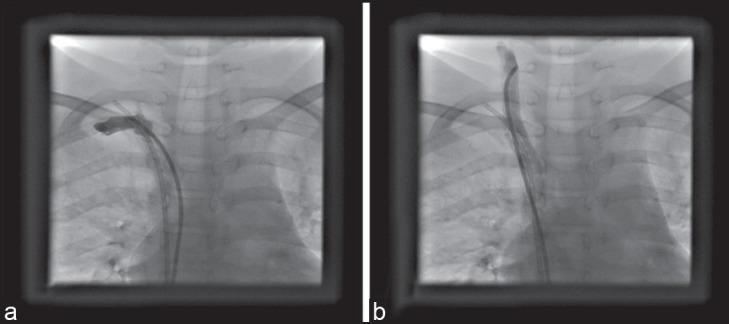

Peripherally inserted venous ports fracture with embolization in patients who received chemotherapy is a serious and rare complication, and few cases have been reported in children. We report a successful endovascular technique using a snare for retrieving broken peripherally inserted venous ports in a child for chemotherapy. Catheter fragments may cause complications such as cardiac perforation, arrhythmias, sepsis, and pulmonary embolism. A 12-year-old female received chemotherapy for acute lymphocytic leukemia through a central venous port implanted into her right subclavian area. The patient completed chemotherapy without complications 6 months ago. Venous port was accidentally fractured during its removal. Chest radiographs of the patient revealed intracardiac catheter fragment extending from the right subclavian to the right atrium (RA) and looping in the RA. The procedure was performed under ketamine and midazolam anesthesia and fluoroscopic guidance using a percutaneous femoral vein approach. A snare with triple loops (10 mm in diameter) was used to successfully retrieve the catheter fragments without any complication. Percutaneous transcatheter retrieval of catheter fragments is occasionally extremely useful and should be considered by interventional cardiologists for retrieving migrated catheters and can be chosen before resorting to surgery, which has potential risks related to thoracotomy, cardiopulmonary bypass, and general anesthesia.

接受化疗的患者外周静脉植入端口发生断裂并栓塞是一种严重且罕见的并发症,儿童病例报道较少。我们报告了一种成功的血管内技术,使用圈套器为一名接受化疗的儿童取出断裂的外周静脉植入端口。导管碎片可能导致心脏穿孔、心律失常、败血症和肺栓塞等并发症。一名12岁女性通过植入右锁骨下区域的中心静脉端口接受急性淋巴细胞白血病化疗。患者6个月前完成化疗,无并发症。在取出静脉端口时意外发生断裂。患者胸部X线片显示心内导管碎片从右锁骨下延伸至右心房(RA)并在RA内呈环状。该操作在氯胺酮和咪达唑仑麻醉下,采用经皮股静脉途径在透视引导下进行。使用一个直径10毫米的三环圈套器成功取出导管碎片,无任何并发症。经皮经导管取出导管碎片偶尔非常有用,介入心脏病学家在取出移位导管时应予以考虑,并且在诉诸有开胸、体外循环和全身麻醉相关潜在风险的手术之前可以选择该方法。